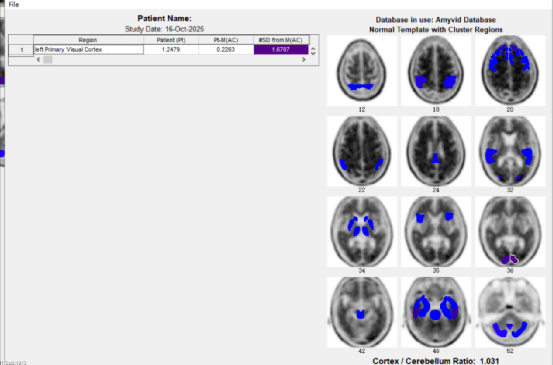

患者aβ-淀粉样蛋白 PET/CT图像:(显像剂:18F-AV45)

诊断意见:大脑双侧枕叶皮质初级视觉皮层aβ淀粉样蛋白(轻度)沉积阳性,以左侧为主。